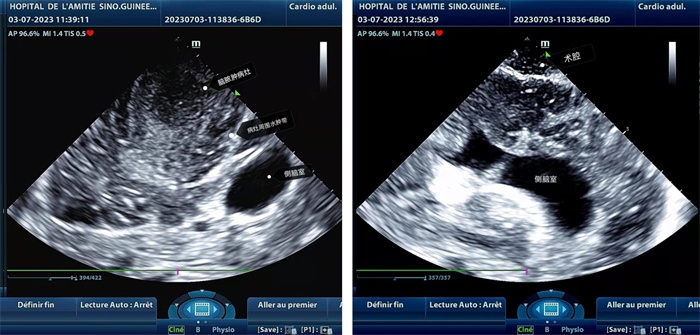

左圖顯示術中超聲見囊實性病變,大小約為4x4x3cm,病灶周圍腦組織水腫明顯;右圖為病灶切除后,術中超聲示術腔無病變殘留

手術中,張國濱在超聲科顧秀娟的幫助下,運用顱腦術中超聲技術,通過將一次性保護套的超聲探頭置于腦組織表面,實時觀察病變的位置和形態(tài),進一步確認最佳手術路徑。術中超聲顯示,病變位于左額頂葉,大小約為4x4x3cm,邊界清晰,呈囊實性,周邊腦組織水腫明顯。最終,病灶順利切除,診斷為腦膿腫,并通過超聲檢測確認術腔無病變殘留、無出血,為患者術后恢復提供了良好的保障。